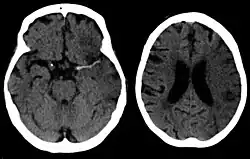

Silent stroke

Silent stroke is stroke that does not have any outward symptoms, and people are typically unaware they had experienced stroke. Despite not causing identifiable symptoms, silent stroke still damages the brain and places the person at increased risk for both transient ischemic attack and major stroke in the future. Conversely, those who have had major stroke are also at risk of having silent stroke.[62] In a broad study in 1998, more than 11 million people were estimated to have experienced stroke in the United States. Approximately 770,000 of these were symptomatic and 11 million were first-ever silent MRI infarcts or hemorrhages. Silent stroke typically causes lesions which are detected via the use of neuroimaging such as MRI. Silent stroke is estimated to occur at five times the rate of symptomatic stroke.[63][64] The risk of silent stroke increases with age, but they may also affect younger adults and children, especially those with acute anemia.[63][65]

For detecting chronic hemorrhages, an MRI scan is more sensitive.[78]

CT scans may not detect ischemic stroke, especially if it is small, of recent onset,[10] or in the brainstem or cerebellum areas (posterior circulation infarct). MRI is better at detecting a posterior circulation infarct with diffusion-weighted imaging.[79] A CT scan is used more to rule out certain stroke mimics and detect bleeding.[10] The presence of leptomeningeal collateral circulation in the brain is associated with better clinical outcomes after recanalization treatment.[80] Cerebrovascular reserve capacity is another factor that affects stroke outcome – it is the amount of increase in cerebral blood flow after a purposeful stimulation of blood flow by the physician, such as by giving inhaled carbon dioxide or intravenous acetazolamide. The increase in blood flow can be measured by PET scan or transcranial doppler sonography.[81] However, in people with obstruction of the internal carotid artery of one side, the presence of leptomeningeal collateral circulation is associated with reduced cerebral reserve capacity.[82]